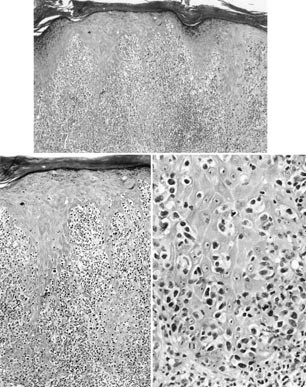

All cases revealed similar histopathologic findings (Fig. 2). The epidermis (the mucosa in Case 5) was markedly acanthotic and infiltrated by atypical mononuclear cells with a moderate amount of lightly eosinophilic cytoplasm. The cells were larger than mature lymphoid cells and contained a large nucleus with irregular borders. The nucleus was surrounded by a clear space (halo) that replaced most of the cytoplasm (Fig. 2C). A much less striking dermal inflammatory infiltrate was also present. The dermal infiltrate was composed predominantly of mature and reactive lymphocytes, histiocytes, and a few plasma cells. Eosinophils were not identified in any of the biopsies. Atypical mononuclear cells either were absent or were present only in small numbers in the dermal infiltrate.

Histopathologic appearance of pagetoid reticulosis. The epidermis is markedly acanthotic and covered by hyperkeratosis and parakeratosis (A). Particularly, the lower half of the epidermis is infiltrated by atypical lymphoid cells with enlarged, hyperchromatic and hyperconvoluted nuclei; irregular nuclear outlines; and abundant, clear cytoplasm (B and C).